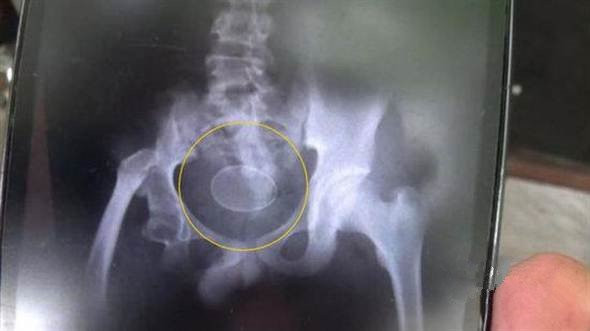

Sau khi chụp X-quang, các bác sỹ phát hiện ra ở khoang xương chậu của cậu bé 12 tuổi có một vật hình bầu dục, nhưng không thể giải thích được đó là gì.

Hình ảnh chụp X-quang cho thấy dị vật trong phần xương chậu của Akmal.

Một giờ sau đó, Akmal tiếp tục đẻ 7 quả trứng nữa. Bác sỹ Ferliyan, một trong những người thực hiện chụp X-quang cho Akmal thừa nhận đội ngũ nhân viên y tế không thể tìm ra nguyên nhân gây ra hiện tượng cực kỳ hiếm gặp này.